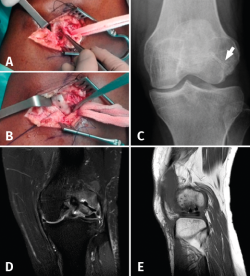

The initial radiographs revealed fracture of the external femoral condyle with an osteochondral fragment lodged in the lateral femorotibial joint space (Figure 1A). This displacement was not confirmed at radiological controls following immobilization (Figure 1B). Computed axial tomography (CAT) revealed a non-displaced double fracture line at the posterior margin of the external femoral condyle, parallel to the joint surface of the latter and measuring 21 mm in length, together with signs of avulsion fracture at the medial margin of the patella, with lateral subluxation (Figure 1B).

Figure 1. A: anteroposterior radiograph of the left knee. Osteochondral fragment of the external femoral condyle (arrow); B: reduced fragment in the initial anterosuperior radiograph (arrowhead); C: axial view; and D: coronal view of the initial CAT scan showing the osteochondral fracture without displacement (arrowhead); E: CAT coronal view showing fracture avulsion at the medial margin of the patella, with lateral patellar subluxation due to involvement of the medial retinaculum (arrow); F: MRI sagittal view showing the fragment and tendon of the TP; G: MRI coronal view showing bone edema of the external femoral condyle (white arrow) and subluxation of the TP (asterisk), together with horizontalization of the osteochondral fragment and a hyperintense image corresponding to rupture in the external meniscus with a pseudodiscoid appearance (black arrows).

At reassessment after 12 weeks, the patient reported "joint laxity" and "failing" of the knee. The physical examination revealed altered gait with great patient apprehensiveness and a tendency towards a "varus drive" pattern, overjet in the lateral femorotibial compartment with mild laxity +/+++ in varus and 0 and 30 degrees of flexion, together with an inconclusive dial test. The Lachman and anterior and posterior drawer in neutral rotation manoeuvres proved negative. The posterolateral rotary drawer test showed subtle asymmetry, with a joint balance of 0 at 115 degrees. The MRI study revealed a subchondral lesion in the loading zone of the external femoral condyle accompanied by intense bone edema and joint effusion. The external meniscus presented a pseudo-discoid appearance with suspected rupture (Figure 1C-D).